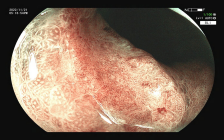

图示:结肠高分化腺癌:镜下呈隆起病变,放大内镜观察:表面结构不规则,微血管扭曲、紊乱、不规则。